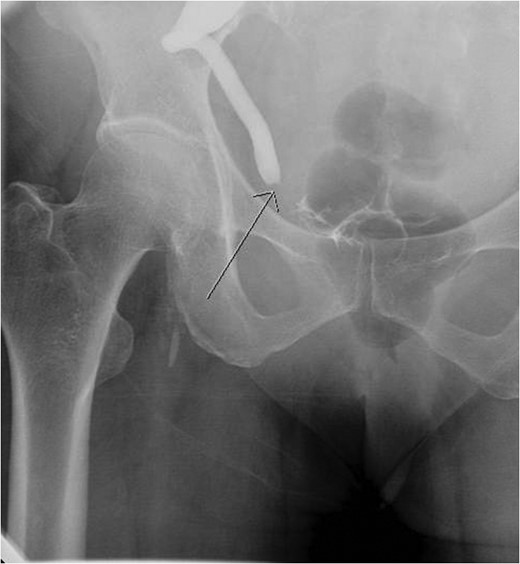

Aterograde nephrostogram demonstrating the obstruction at the ureterovesical junction.